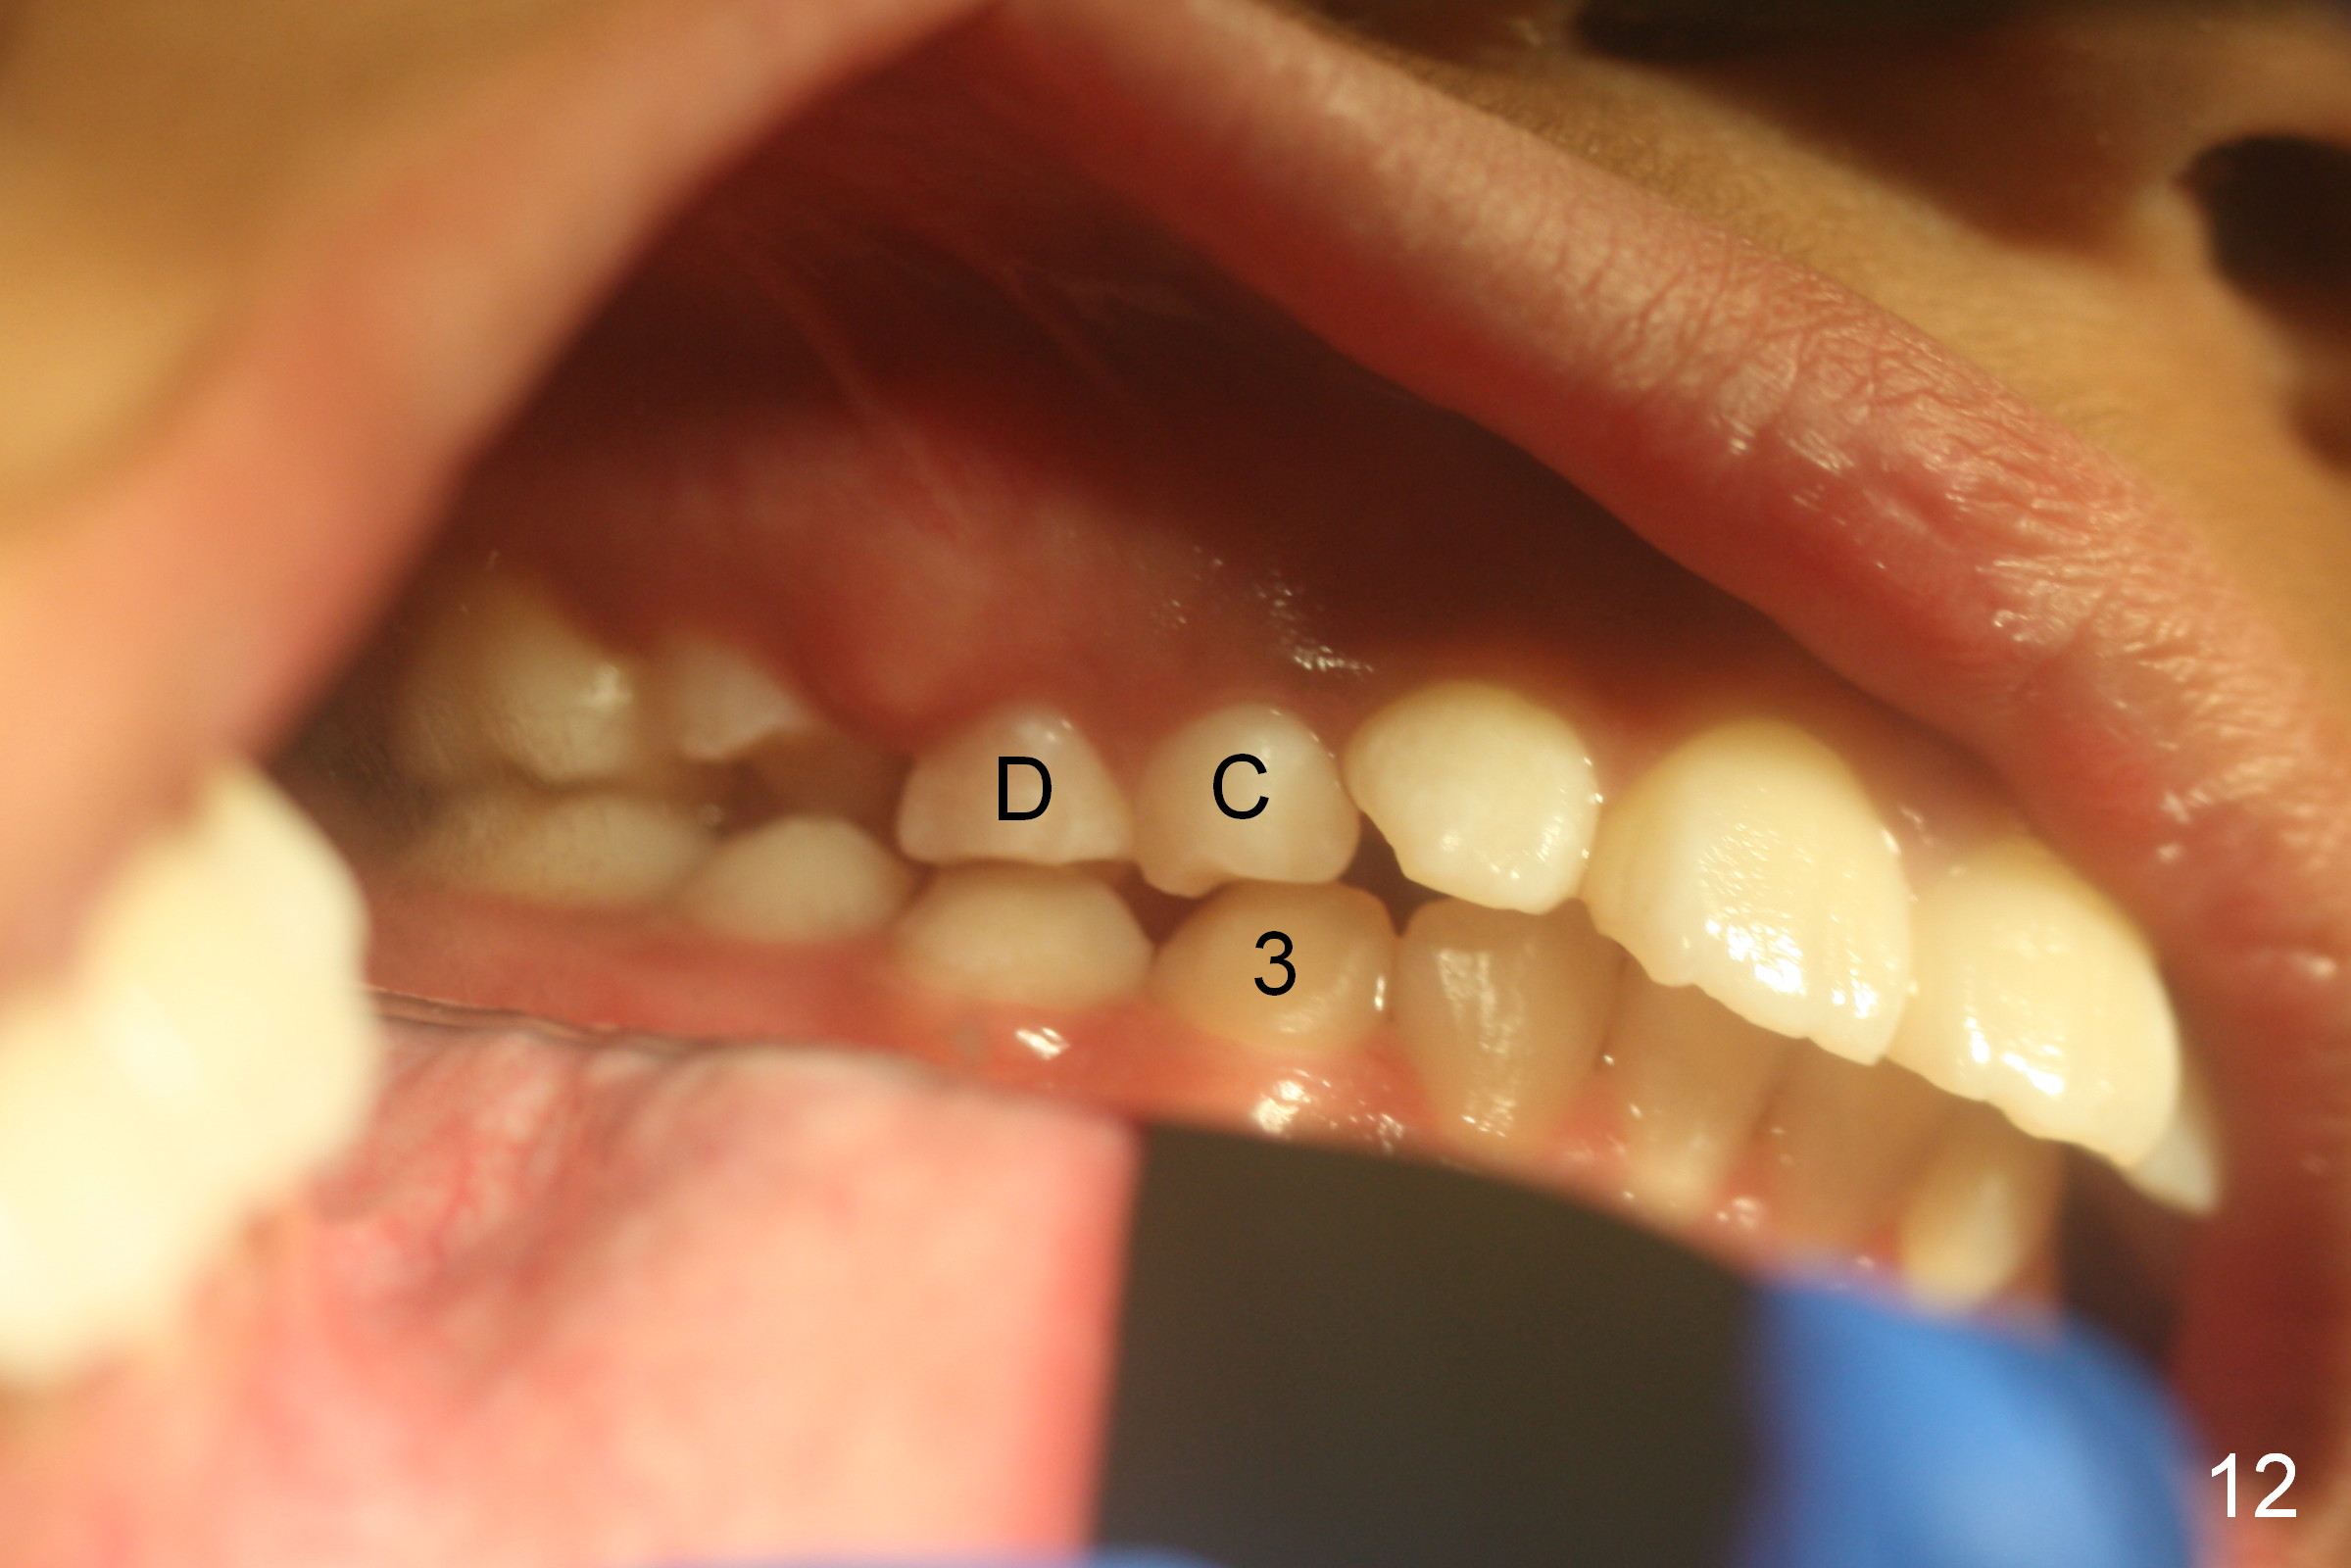

A 11-year-old boy has history of asthma. His father has sleep apnea with similar Class II malocclusion. Pan was taken for the boy 3 years ago (Fig.1). His mother wants to have orthodontic treatment as early as possible, because of protrusive upper anterior teeth. The dentition is permanent except the upper left canine and 1st molar (Fig.7,10,12,13 C, D). It appears that there is bilateral Class II occlusion at canine by half a tooth (Fig.9-12). The malocclusion and facial profile can be easily corrected with extraction of the upper 1st bicuspids.